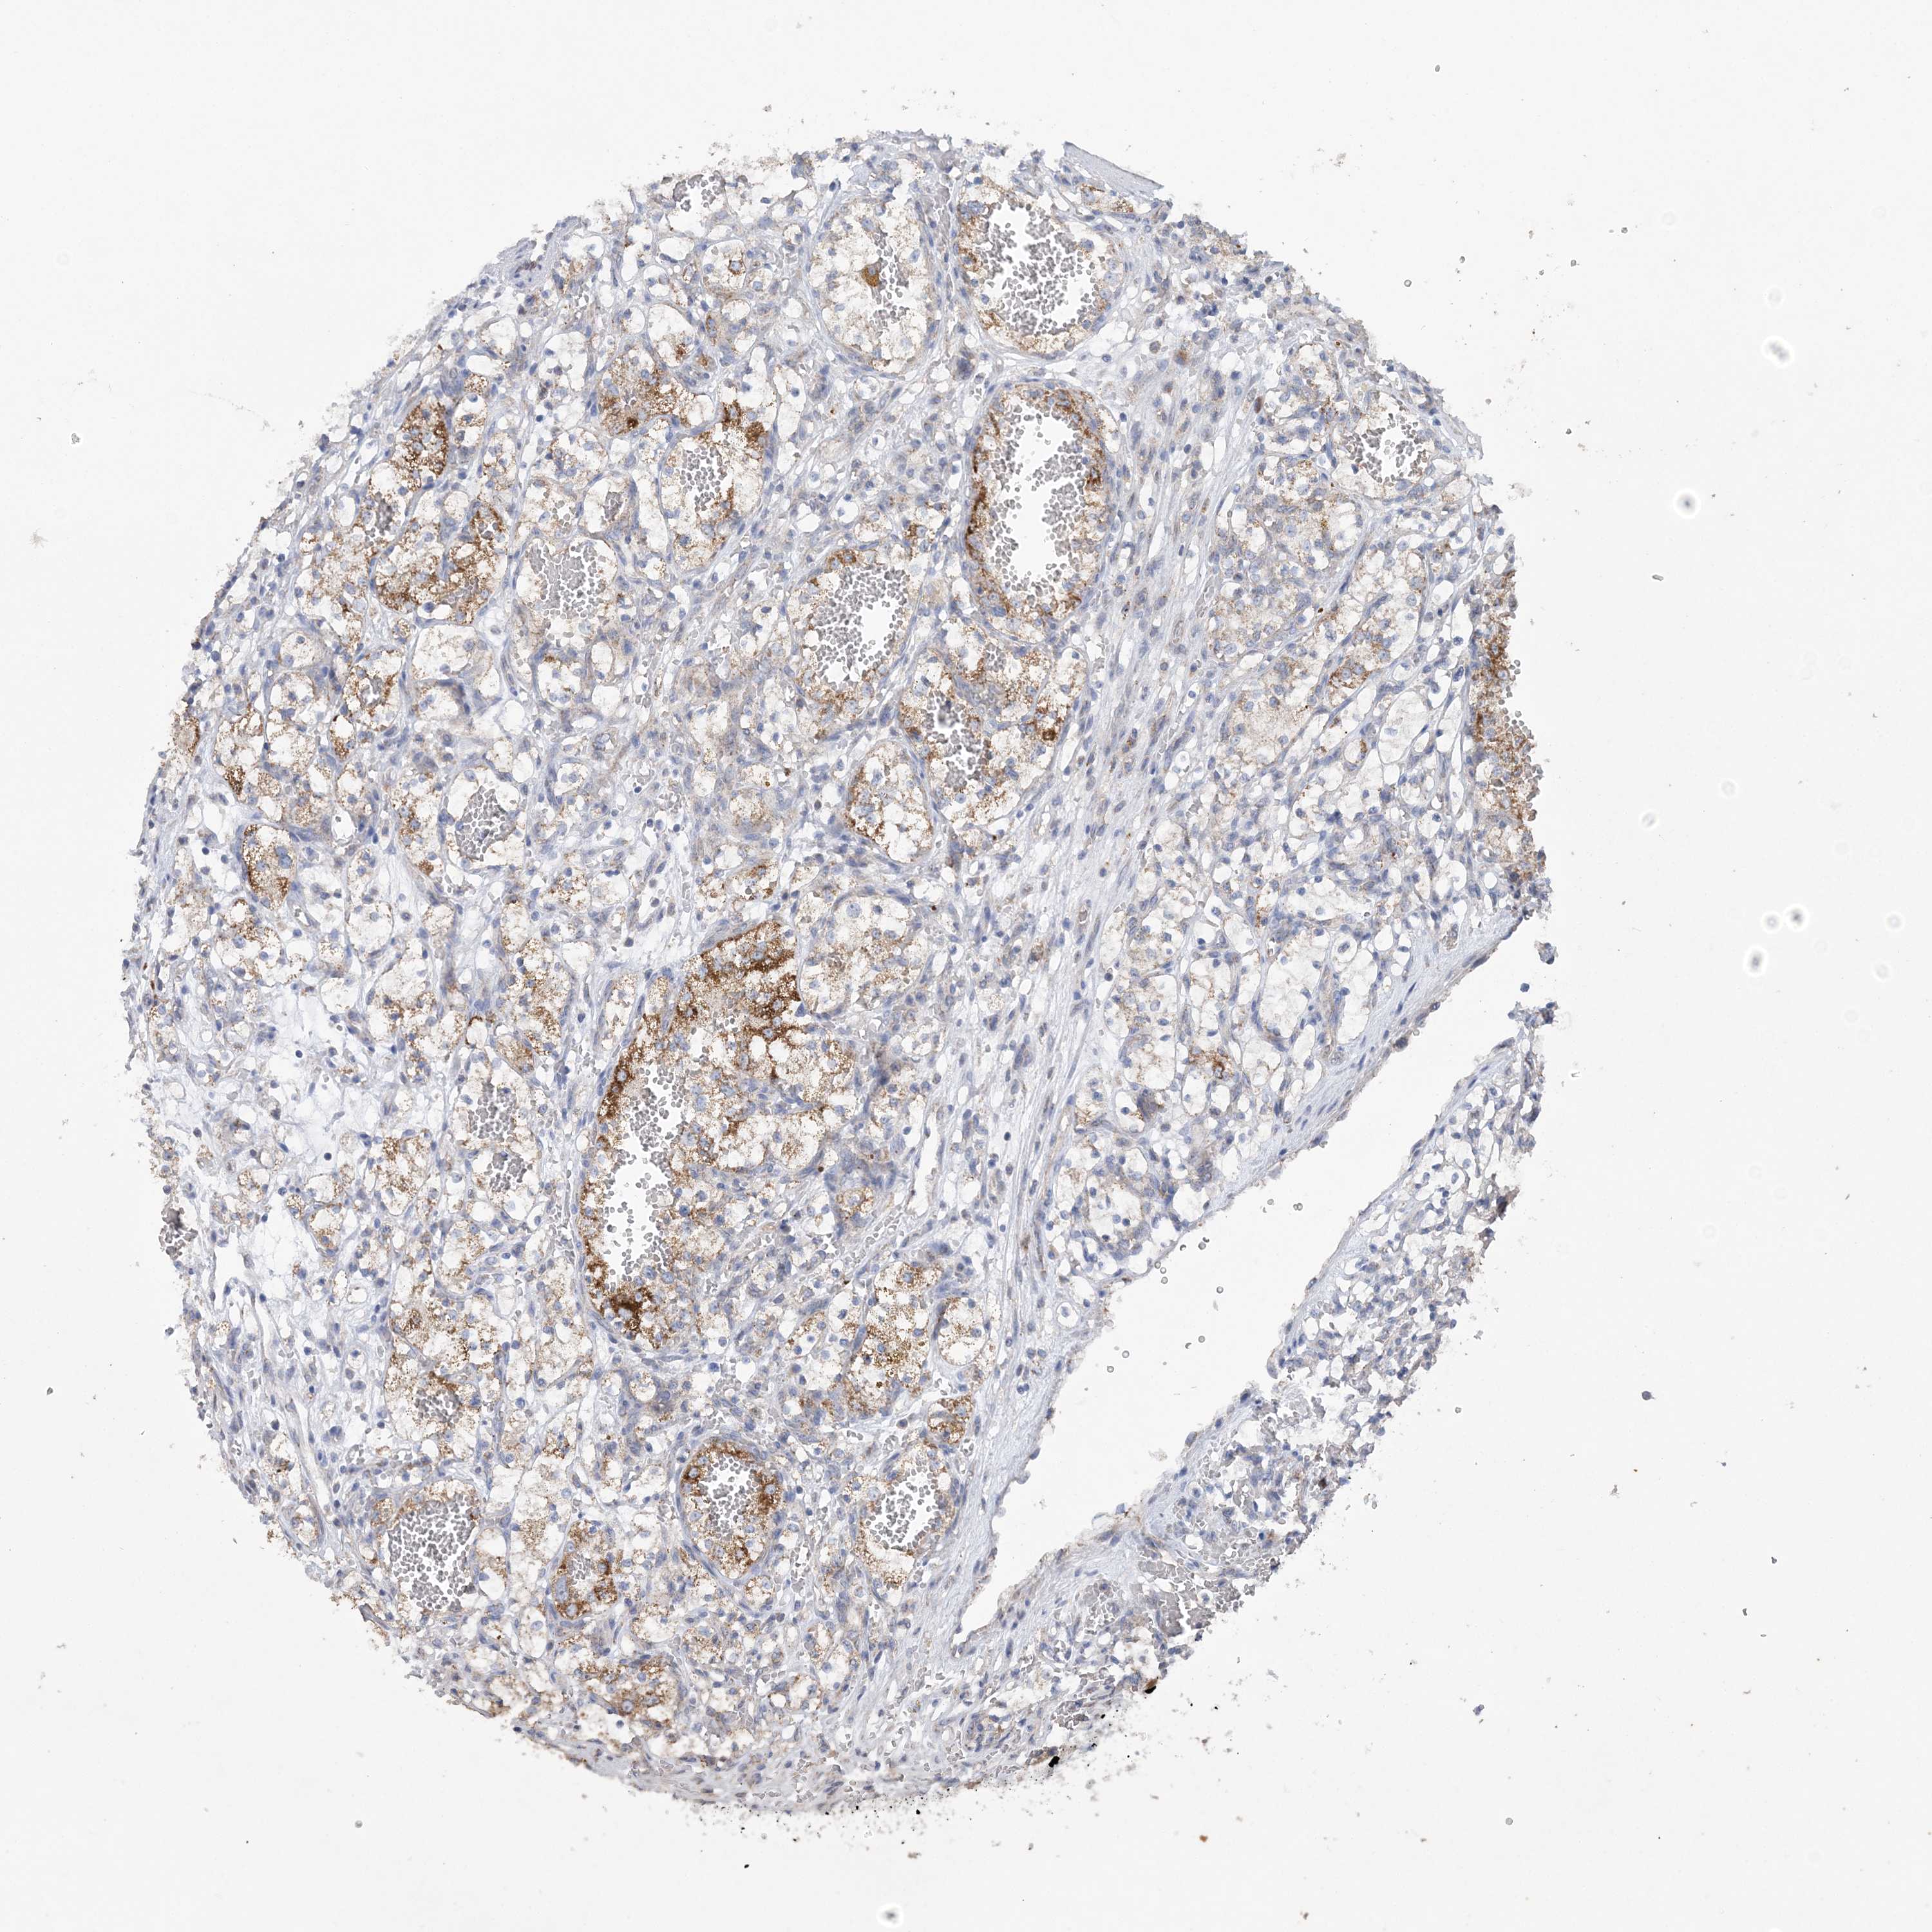

CANCER RENAL CANCER Show tissue menu

KICH TCGA KIRC TCGA KIRC VALIDATION KIRP TCGA PROTEIN RCC CPTAC PROTEIN EXPRESSION